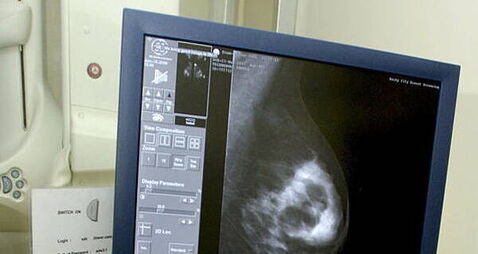

Tipperary nurse sues over alleged delay in breast cancer diagnosisMother of three Aine McSweeney from Clonmel, Co Tipperary also claims that she had two mammograms which she says were allegedly incorrectly interpreted as benign.